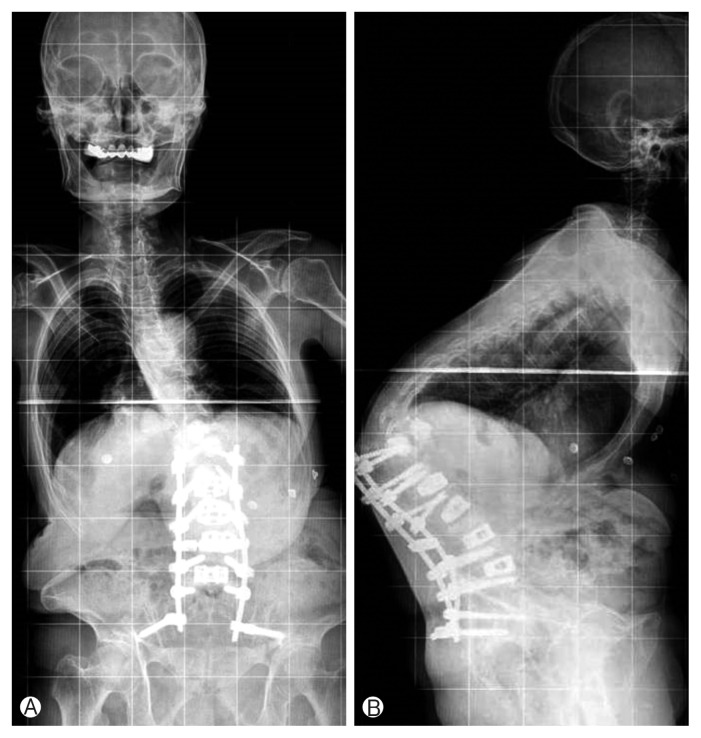

The initial L5-T12 in green posterior fixation turned into S1-T9 in green + yellow + blue for an osteoporotic patient.

In green is what we would give for 100% of the patients as a first procedure: 78% will have a satisfactity clinical outcome.

But 22% of the osteopenic/osteoporotic patients will suffer from BMD related complication with this limited montage.

In blue and yellow: vertebral extention required for the 22% to avoid BMD related complication. Yellow indicates selective pedicle augmentation.